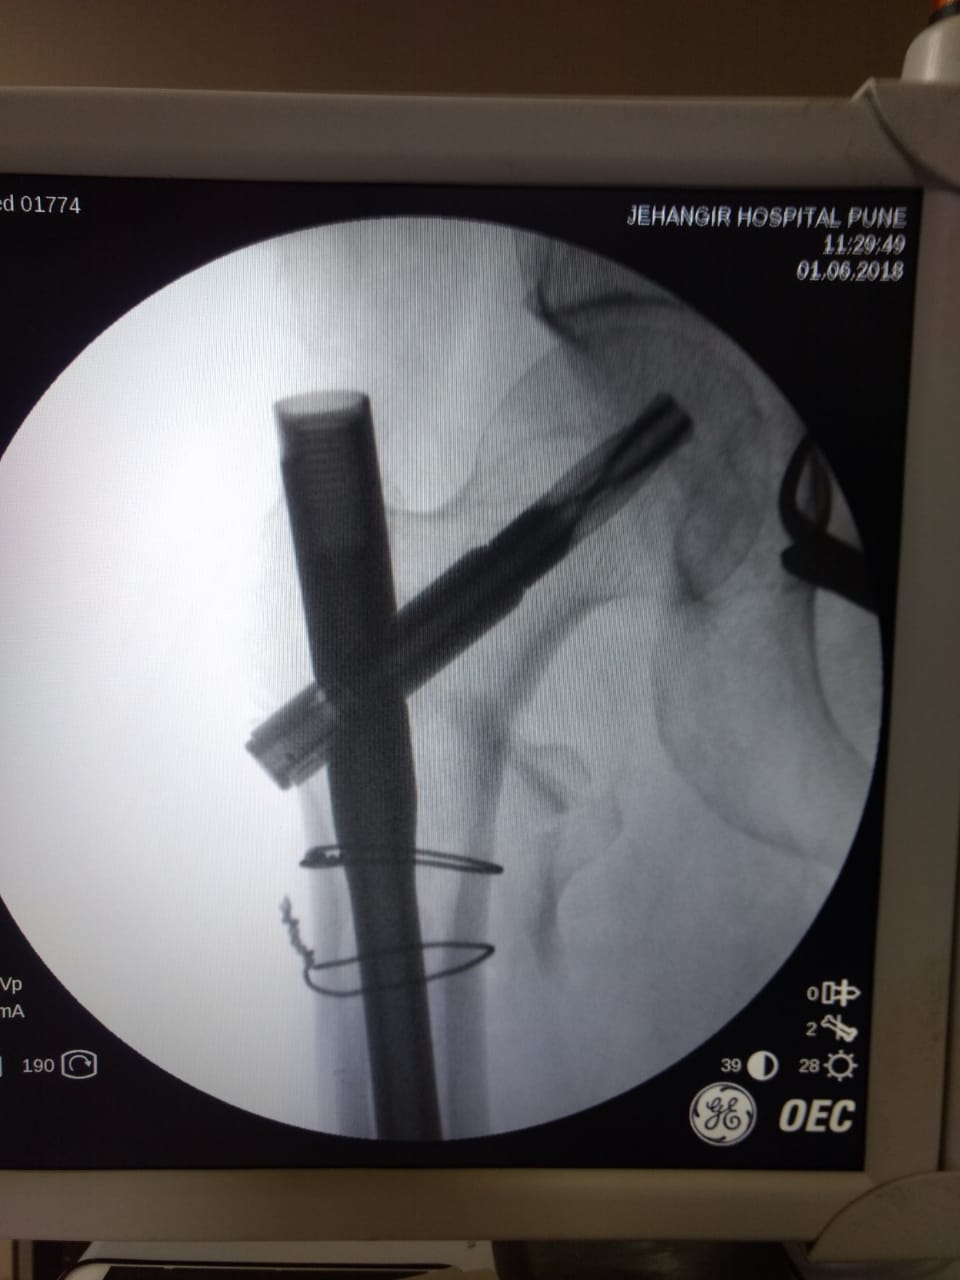

Dr. Sonawane Orthocare clinic is a centrally located Orthopedic Clinic In Pune city near Swargate at Hirabaug Business Centre, Hirabaug chowk, Tilak Road, Shukrawar peth and has easy accessibility from all parts of the city with multiple modes of travelling and enough parking spaces for patients’ own vehicles. Clinic is very modern and stylish and has air conditioned waiting area with comfortable sitting arrangement along with other amenities like TV, Wi-Fi, newspapers. There is hassle-free appointment and consultation system which is totally computerized. Patients get system generated appointment messages, reminders for follow-up dates and prescriptions through messages and emails. So its easy to keep track, keep and carry records and access it anywhere in the world. Clinic offers in-house digital X-ray, pathology tests and physiotherapy facilities at very reasonable rates. This makes the clinic a one stop destination for the patients they don’t need to go anywhere else for these facilities, saving lots of time and effort to get the treatment. We at Dr. Sonawane Orthocare clinic are committed for the best orthopedics care and proud to be one of the best orthopedics clinics in Pune.